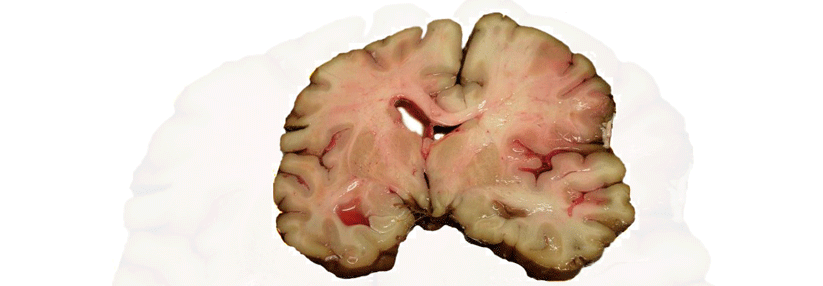

Viele Ärzte fürchten eher die Blutung unter einem „neuen“ oralen Antikoagulans als die Thrombose, die sich ohne Gerinnungshemmung einstellt, kritisierte Professor Dr. Jan Steffel. Er plädierte für einen differenzierten, aber beherzten Umgang mit den NOAK.